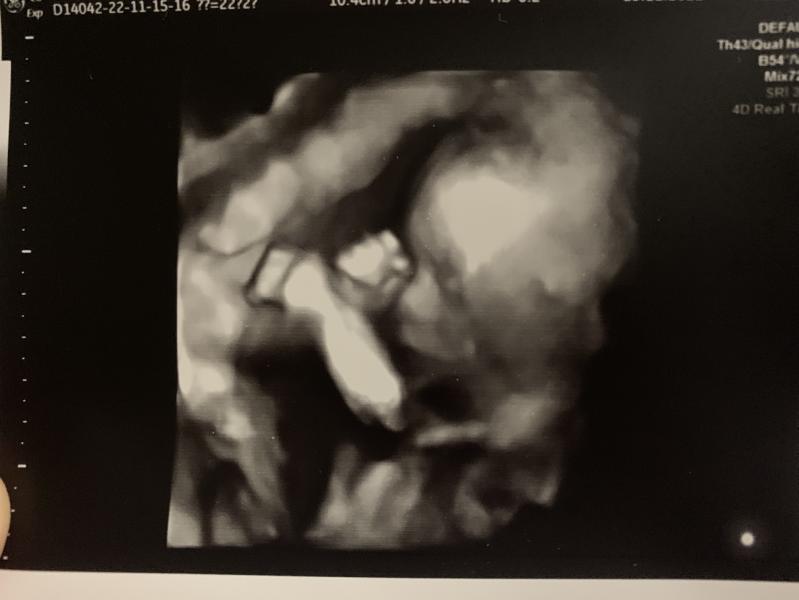

У нас тоже так,но я в пренатальном и не была даже,Темнов с 13 недель сказал девочка,а сейчас даже и фото дал нам нашего богатства)но подружка решила мозг поклевать,доказывает мне обратное,что мальчик и все,что по фото же видно😃😃

В перенатальном увидели девочку, но я решила убедится наверняка))) Темнов с первых секунд это сделал… начал узи со слов… ну вот ваша девочка)))🥰